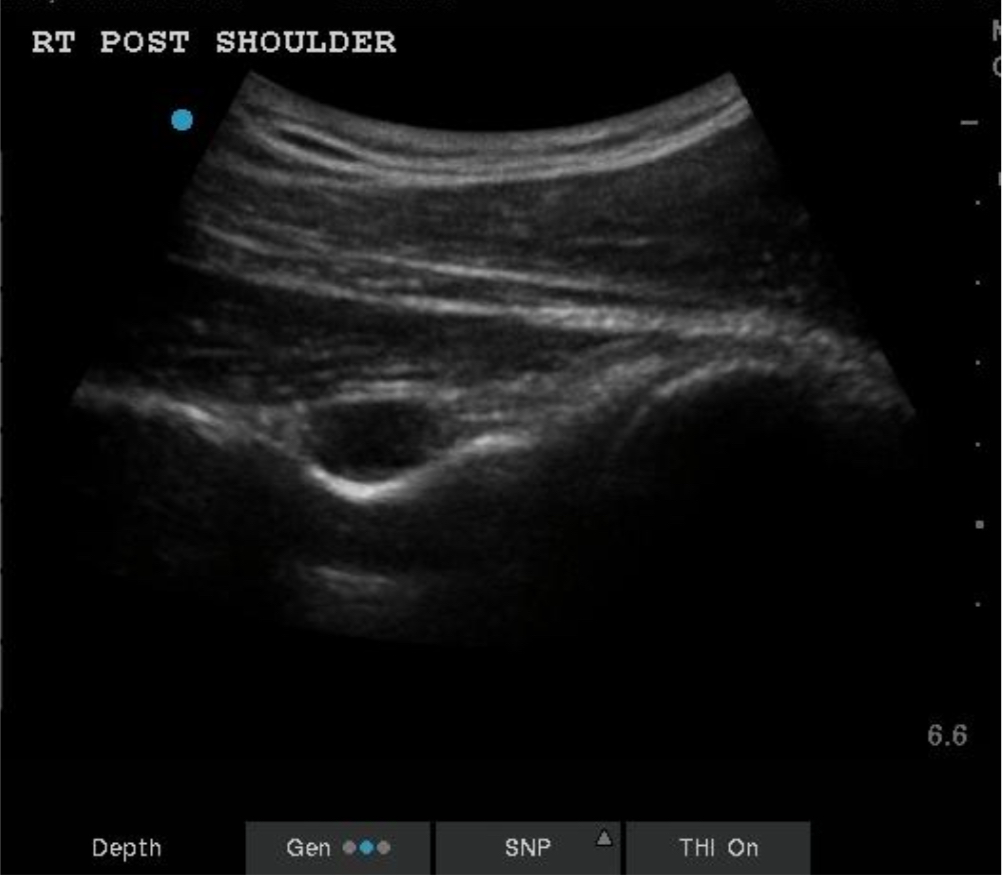

Long axis view of paralabral cyst at the spinoglenoid notch